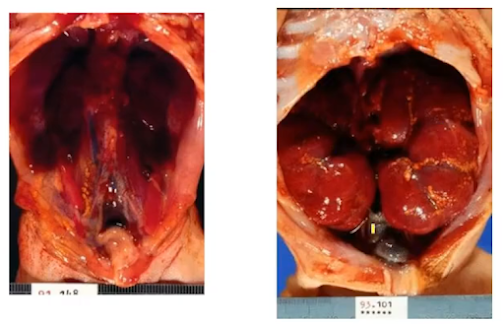

Monstruosidade (termo inapropriado): quando mais de um sistema é afetado gerando figuras fetais bizarras.